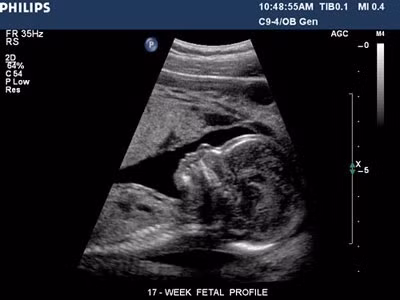

Cách đọc chỉ số siêu âm thai chuẩn xác nhất, mẹ bầu nào cũng cần biết

Bài viết này sẽ hướng dẫn mẹ cách đọc các chỉ số siêu âm thai một cách dễ dàng và chuẩn xác nhất.

Mỗi lần khám, các bác sĩ có thể sẽ thực hiện siêu âm thai để đó chiều dài mông – đùi, đường kính lưỡng đỉnh, chiều dài đầu – mông, cũng như trọng lượng bào thai. Tuy nhiên không phải mẹ bầu nào cũng biết những ký hiệu trên tờ kết quả siêu âm đó.